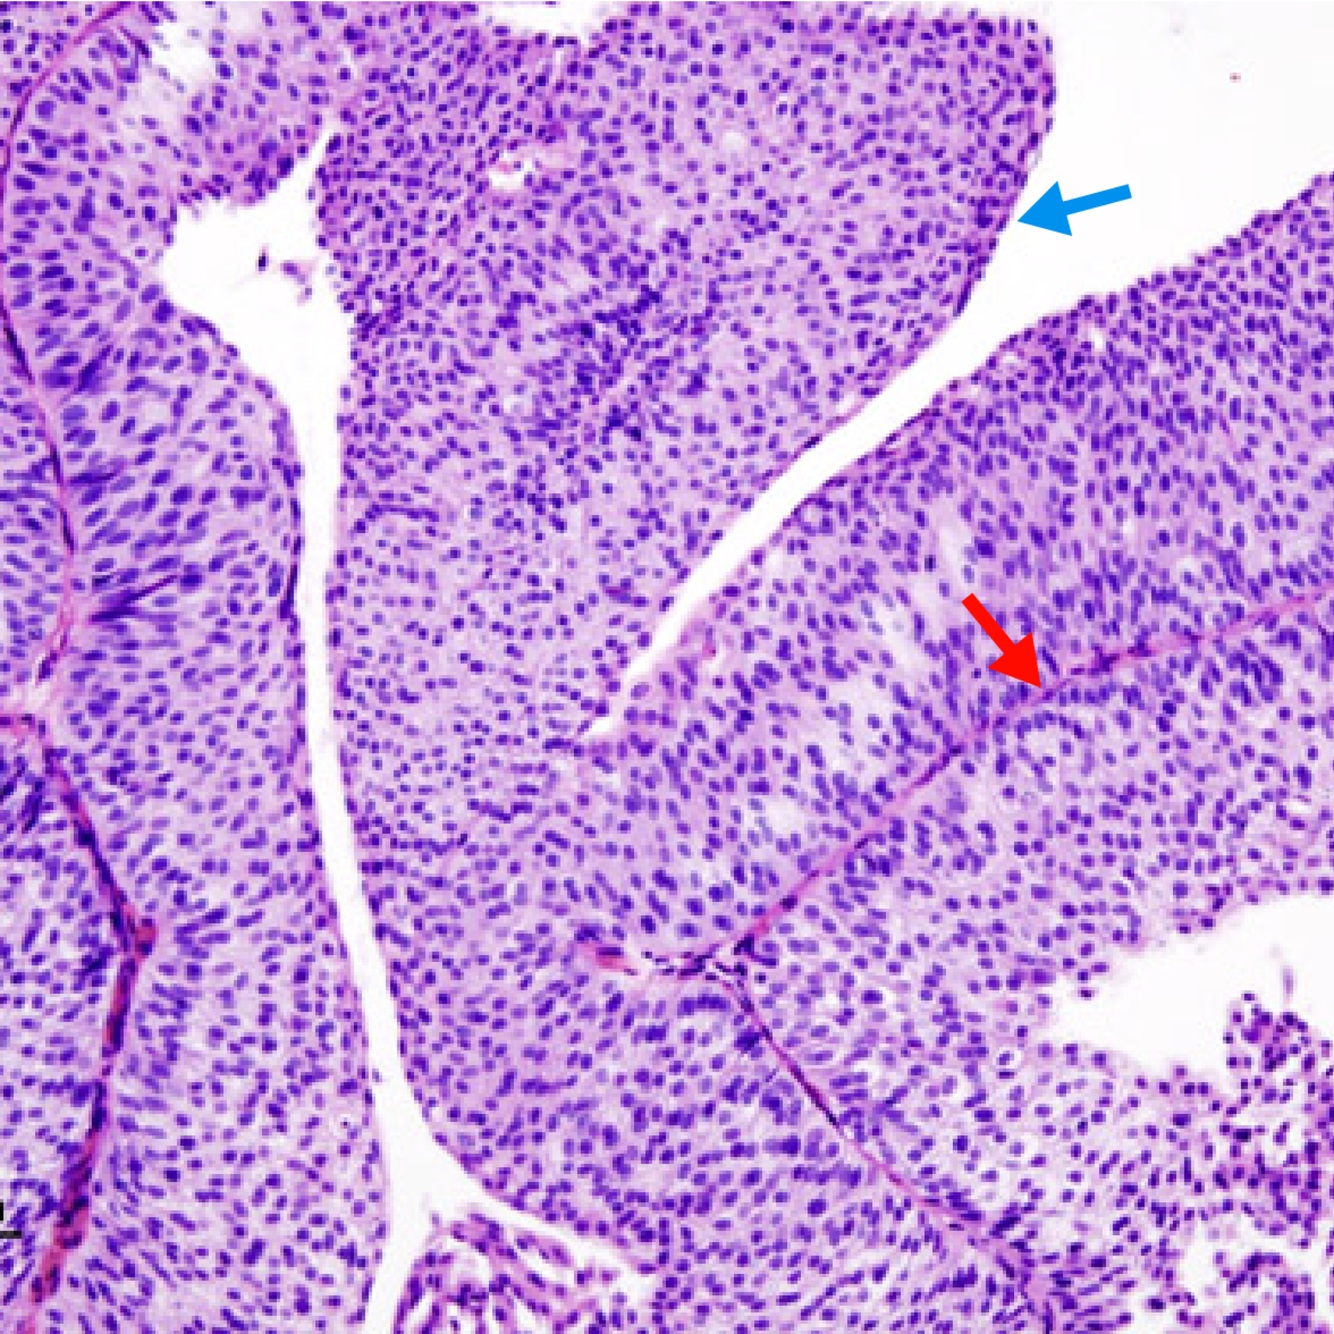

fibrovascular cores (red arrow)

Transtional cell carcinoma of the bladder